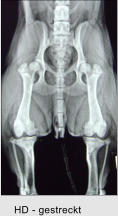

Bartagame - dorsoventral ED - kraniokaudal         gestreckt HD - gestreckt

Röntgen Wir verwenden ein digitales Röntgensystem, dies bietet gleich mehrere Vorteile: Innerhalb von Sekunden ist die Röntgenaufnahme auf dem Monitor sichtbar - lange Wartezeiten, die früher für die Entwicklung notwendig waren, entfallen. Die Aufnahmen können auf Wunsch direkt auf eine CD gebrannt und von Ihnen mitgenommen werden - ein lästiges Hin- und Herschicken entfällt. Im Falle einer notwendigen Überweisung in eine spezialisierte Klinik nehmen Sie die Röntgenaufnahmen für die Kollegin / den Kollegen direkt mit.